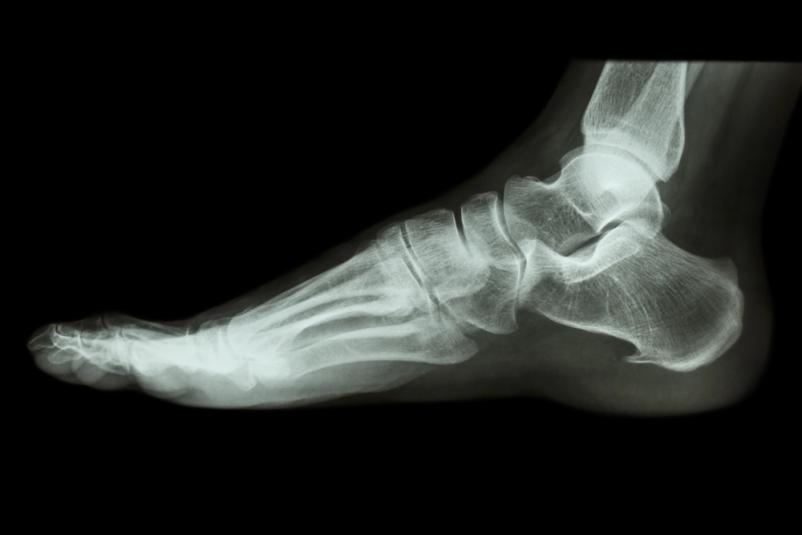

Rentgensko slikanje skeleta je ena osnovnih in najpogosteje uporabljenih diagnostičnih metod v medicini. Omogoča hiter vpogled v stanje kosti, sklepov in drugih struktur ter je nepogrešljivo pri sumu na zlome, degenerativne spremembe ali druge poškodbe. Prav zato je rentgen skeleta brez naročanja izjemno pomembna prednost, saj pacientom omogoča, da so obravnavani pravočasno in brez dodatnega stresa.

Storitev zajema slikanje različnih delov skeleta, pri čemer se uporablja sodobna rentgenska oprema, ki zagotavlja kakovostne in natančne posnetke ob hkratnem upoštevanju vseh varnostnih in strokovnih standardov. Postopek je hiter, neboleč in ga izvajajo izkušeni zdravstveni delavci, usposobljeni za delo na področju radiološke diagnostike.

Rentgen skeleta brez naročanja v ZD Sevnica je posebej primeren v naslednjih primerih: